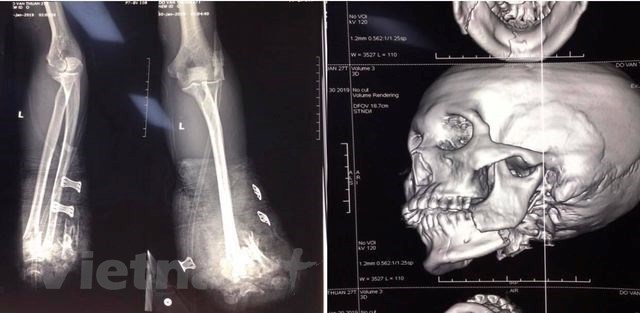

Hình ảnh chụp X-quang về tai nạn thương tích của một bệnh nhân bị tai nạn do pháo nổ tại Bệnh viện Trung ương Quân đội 108. (Ảnh: PV/Vietnam+)

Tối 29/01, các bác sỹ Khoa Cấp cứu (Bệnh viện Trung ương Quân đội 108) đã tiếp nhận bệnh nhân Đỗ Văn T. (25 tuổi, ở Hải Phòng) chuyển đến viện trong tình trạng cụt 2 bàn tay, vết thương vùng hàm mặt, chảy nhiều máu vì tai nạn do pháo nổ tự chế./.